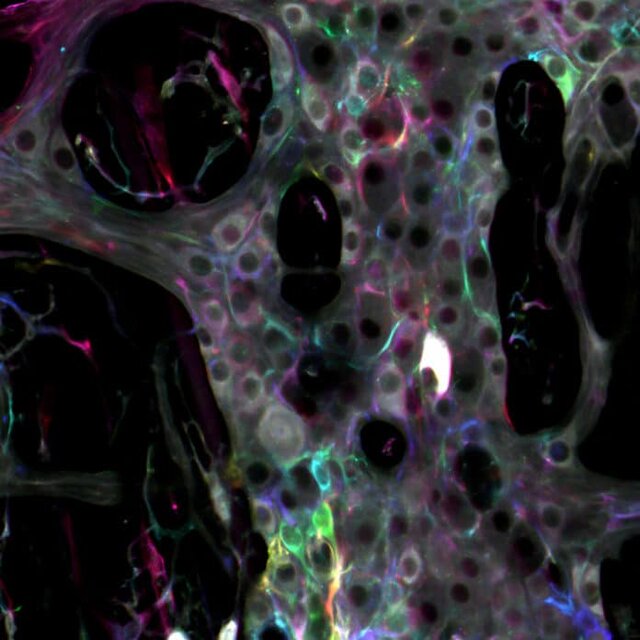

سیستم عصبی رودهای برای مثال مغز دوم روده، یک شبکه پیچیده متشکل از نورونها و گلیا است که رودههای ما را پوشانده است. حال دانشمندان آمریکایی در مطالعه اخیرشان نشان دادهاند که سلولهای گلیا نقش بسیار فعالتری در سیستم عصبی روده دارند.

نتایج مطالعه جدید محققان حاکی از آن است که گلیا دقیقا بر سیگنالهای منتقل شده توسط مدارهای عصبی تاثیر میگذارند.

استاد “برایان گالبرانسن”(Brian Gulbransen) از دانشکده فیزیولوژی دانشگاه ایالتی میشیگان در این باره گفت: اگر مغز دوم را به عنوان رایانه در نظر بگیریم، میتوانیم بگوییم گلیا تراشههایی هستند که عملکرد حاشیهای دارند و عضو فعال پیام رسانی در شبکهاند و کار آنها تعدیل سیگنالها است و مانند نورونها نیستند. علاوه بر این عملکرد، گلیا این موضوع را تایید میکند که همه چیز بدون مشکل در حال انجام است.